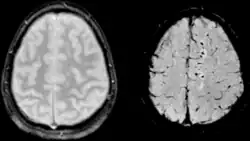

| Two MRI images of a patient with diffuse axonal injury resulting from trauma, at 1.5 tesla field strength. Left: conventional gradient recalled echo (GRE). Right: Susceptibility weighted image (SWI). | |

DAI is difficult to detect since it does not show up well on CT scans or with other macroscopic imaging techniques, though it shows up microscopically.[9] However, there are characteristics typical of DAI that may or may not show up on a CT scan. Diffuse injury has more microscopic injury than macroscopic injury and is difficult to detect with CT and MRI, but its presence can be inferred when small bleeds are visible in the corpus callosum or the cerebral cortex.[34] MRI is more useful than CT for detecting characteristics of diffuse axonal injury in the subacute and chronic time frames.[35] Newer studies such as Diffusion Tensor Imaging are able to demonstrate the degree of white matter fiber tract injury even when the standard MRI is negative. Since axonal damage in DAI is largely a result of secondary biochemical cascades, it has a delayed onset, so a person with DAI who initially appears well may deteriorate later. Thus injury is frequently more severe than is realized, and medical professionals should suspect DAI in any patients whose CT scans appear normal but who have symptoms like unconsciousness.[9]